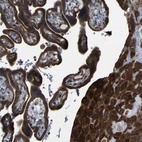

Immunohistochemical staining of human placenta shows strong cytoplasmic positivity in trophoblastic cells and decidual cells.